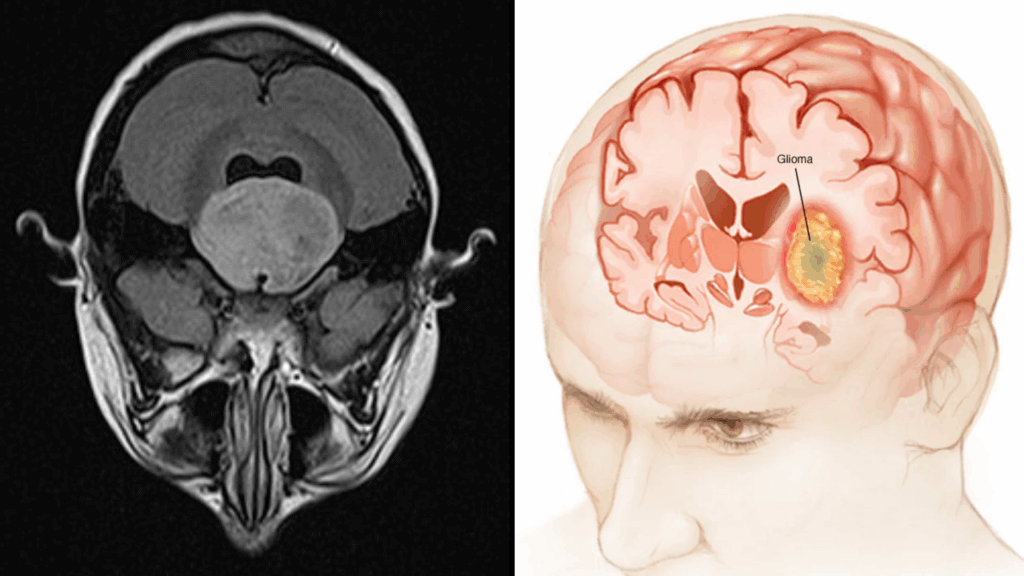

The findings focus on gliomas, a type of brain cancer that originates inside the brain and is notoriously difficult to treat. Unlike many cancers, gliomas spread into healthy brain tissue, making surgery and conventional therapies largely ineffective. Understanding how these tumors interact with surrounding brain cells could be key to finally slowing them down.

Gliomas are especially dangerous because they don’t stay neatly contained. Instead, they weave themselves into normal brain tissue, making complete removal nearly impossible. Survival rates for aggressive gliomas have barely improved over decades, despite advances in cancer treatment elsewhere in the body.